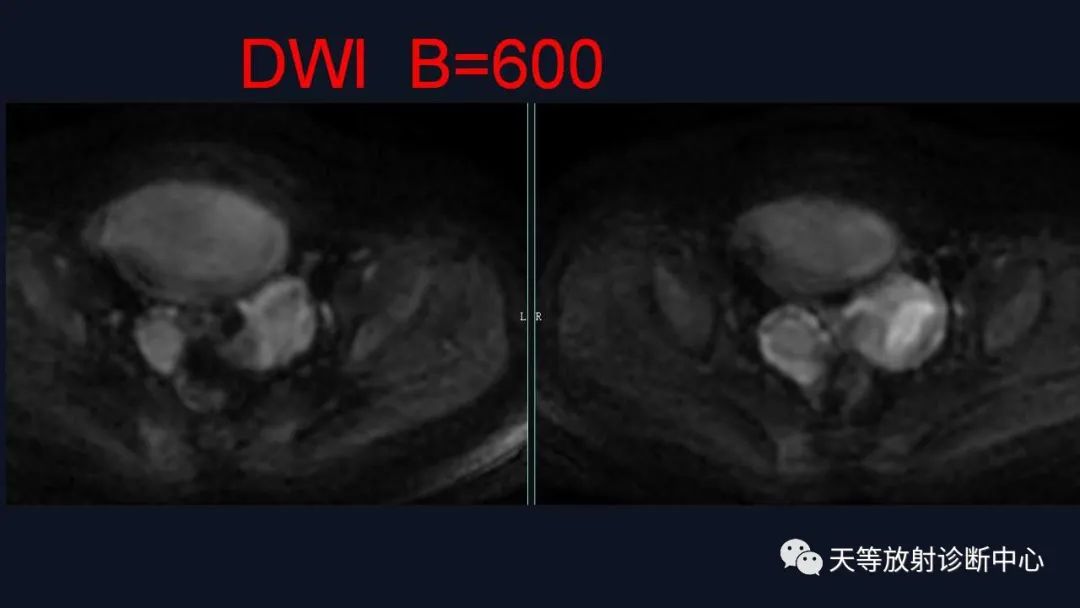

1、浆液性囊腺瘤 :浆液性囊性肿瘤较常见,浆液性肿瘤好发的平均年龄为40岁以上,表现为纯囊性,可呈多囊改变,T1WI呈低信号、T2WI呈高信号、DWI呈低信号,增强后无实性成分强化。

交界性肿块呈囊实性、多房改变, T1WI呈高信号、T2WI呈高信号、病灶实性部分DWI以较高信号为主,增强后实性成分均呈结节状强化。